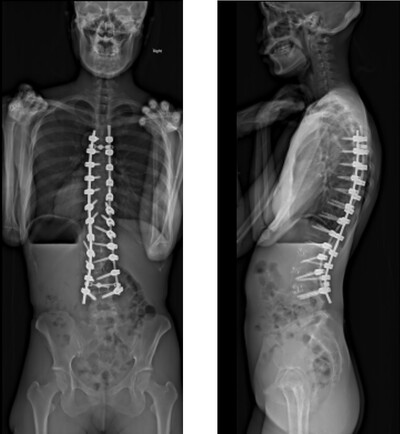

思春期特発性側弯症の全脊椎レントゲンで背骨が大きくSの字に曲がっています。最も曲がっている箇所は80°で、高度側弯に分類されます。後方からの脊柱側弯矯正術で真っ直ぐになっています。

また、側弯の患者さんは一般的にフラットバックと言って背骨の生理的後弯(背中の丸み)が失われています。この症例も胸椎後弯角は5°で典型的なフラットバックを呈しています(正常は20°~30°程度です)。この影響は頸椎の形態にも影響を及ぼし、この症例も頸椎が既に後弯(正常は前弯)しています。(黄色矢印)

ストレートネックという頸椎の前弯が消失して頸部の愁訴が出現する病態は広く知られていますが、更に変形が進行した頸椎と考えて下さい。

以前はこのフラットバック(生理的胸椎後弯の消失)を治すことは困難でしたが、当院では手術方法の様々な工夫により生理的胸椎後弯の復元を行っております。この症例は術後に胸椎後弯角が26°と改善しており、生理的な胸椎後弯が形成されています。さらに頸椎後弯にも良い影響を及ぼし、術後は頸椎前弯化が得られつつあるのが分かります。(黄色矢印)

他、側弯変形は必ず大なり小なりの回旋変形を伴います。脊柱の回旋変形は胸郭(肋骨)の回旋につながり、これにより側弯の患者さんは背中の片方が出っ張っています(多くは右)。リブハンプと言いますが、脊柱変形矯正によりこの回旋変形も改善します。この症例も術前に肋骨がかなり隆起していますが、術後にこの隆起がかなり減じているのが分かります。(赤矢印)